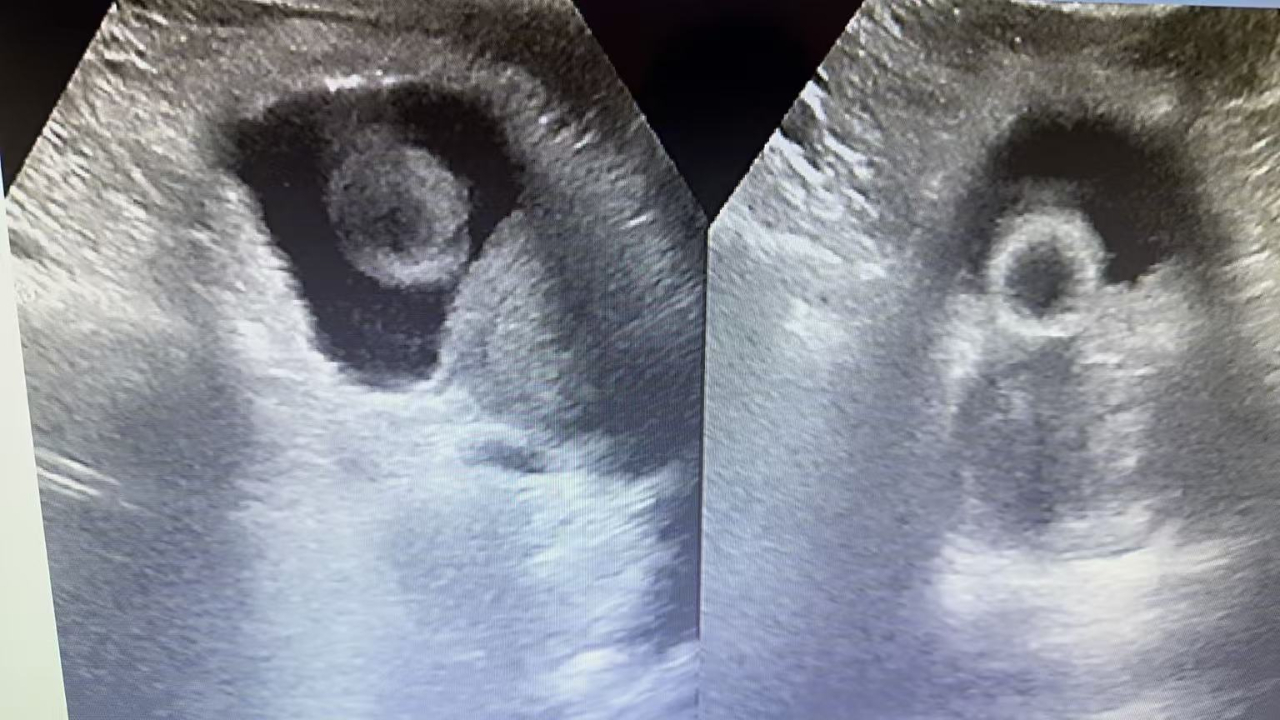

近期 我院普外科连续为两位80多岁高龄的男性患者成功实施了经尿道前列腺电切术。两位患者均因“进行性排尿困难2年,夜尿频(初始每晚7次,渐加重至10次左右)、尿潴留、血尿”反复留置导尿而长期困扰。术前经过麻醉科、心内科等多学科联合评估,精准把控手术指征与风险,确认患者虽然高龄,但手术耐受性良好。 通过内镜微创手术操作,精准切除增生腺体,迅速解除了尿道梗阻。在现代麻醉与微创外科技术的支持下,高龄本身不再是手术的绝对禁区。关键在于由专业团队进行系统、审慎的围手术期评估与管理。 患者安返病房 老年男性前列腺增生极为常见,严重影响着生活质量,夜尿多休息不好,极易引起心脑血管疾病等并发症。许多患者常因“年纪大了,忍一忍”或“害怕手术”而延误治疗,导致反复尿潴留、泌尿系感染、甚至肾功能损害,以至于失去手术治疗机会。 经尿道前列腺电切术作为成熟微创术式,具有创伤小、恢复快、出血少等优势,能有效改善排尿功能,显著提升晚年生活质量。 希望借此案例,提醒广大中老年朋友。若出现尿线变细、起夜频繁、排尿费力等症状,请尽早到泌尿外科就诊。健康不分年龄,科学评估+积极干预,方能畅享晚年。 普外科 联系电话 0431-76297370 联系地址 公主岭市河南广场阳光医院一楼门诊2号诊室